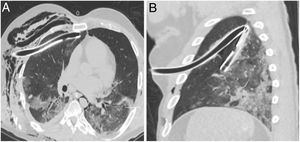

Regarding medical devices, they were removed in two patients prior to performing the PMCT. Still, we could identify the incorrect positioning of some devices in 80% of the remaining cases, being the most common incorrect position the inadequate placement of the endotracheal tube in relation to the carina. The most severe case was the incorrect placement of 2 chest tubes in the same patient, as shown in Fig. 2.